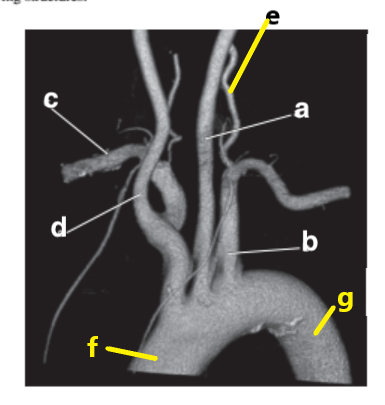

Subclavian artery

Vertebral artery

Aortic arch

a

Abdominal aorta

f

Ascending aorta

Descending aorta

Carotid bifurcation